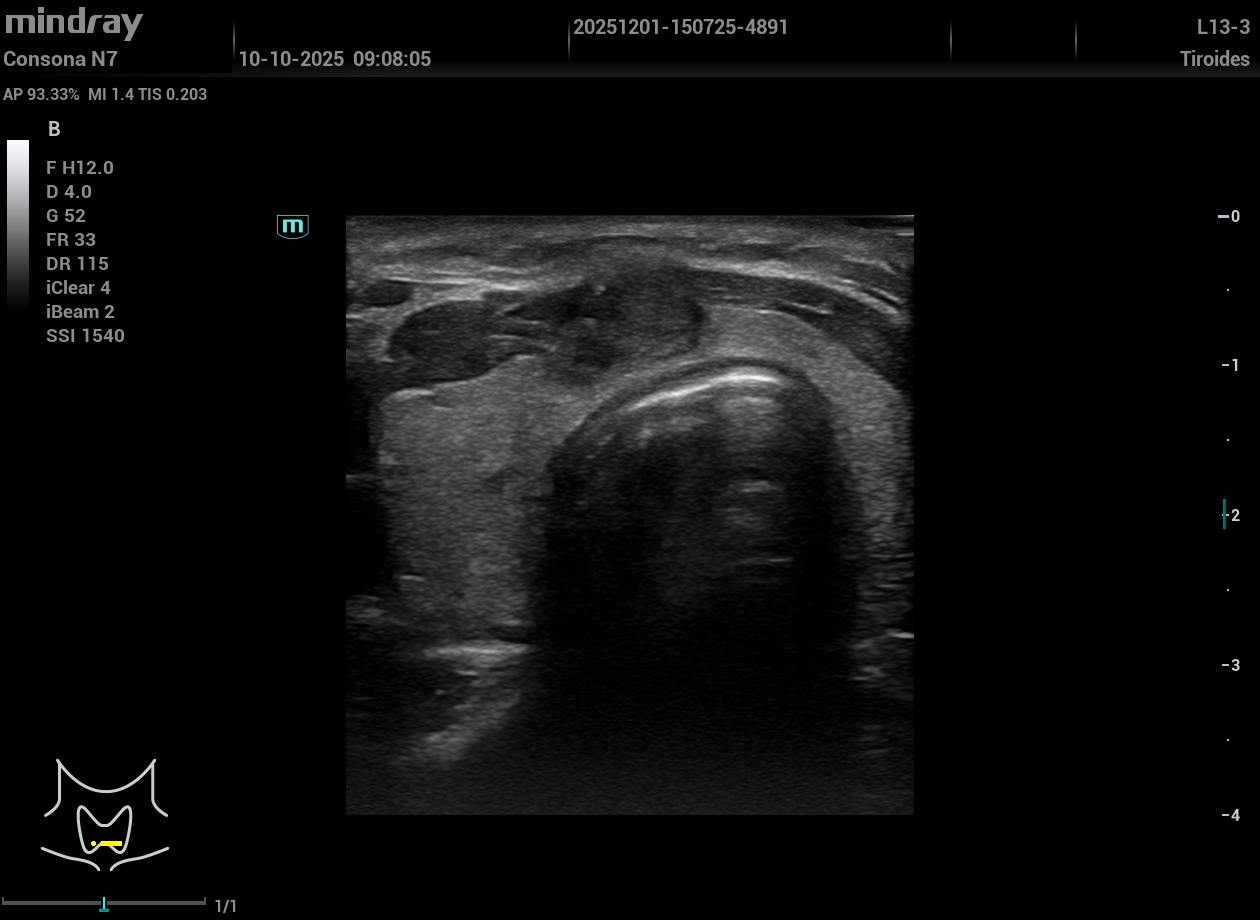

Exploración Física: Nódulo visible y palpable en línea media cervical anterior a la altura de la glándula tiroidea, no doloroso. Tras la exploración manual y dada la reciente aparición del nódulo realizamos ecografía en el momento.

Exploración ecográfica. Se observa un tiroides de tamaño y ecogenicidad normal y en istmo un nódulo hipoecogénico de aspecto heterogéneo, lobulado de bordes parcialmente delimitados, que se extiende fuera de la glándula, DE 14,3 mm de eje mayor, vascularizado y aspecto ecográfico sospechoso. TIRADS 5.

No se aprecian adenopatías patológicas.